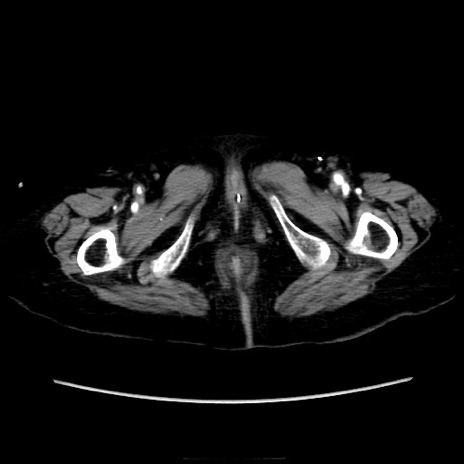

症例40(横断像)

【症例】90歳代女性

【主訴】腹痛・嘔吐

【現病歴】 食欲低下、嘔吐があり昨日他院受診。肺炎と診断され入院となる。入院後より腹部全体に圧痛あり。胃管留置され経過みていたが、症状持続するため、

当院転院となる。

【既往歴】胸椎圧迫骨折、胆石症

【身体所見】腹部:中央に激痛あり、圧痛あり、反跳痛不明

【データ】WBC 17100、CRP 18.82

横断像